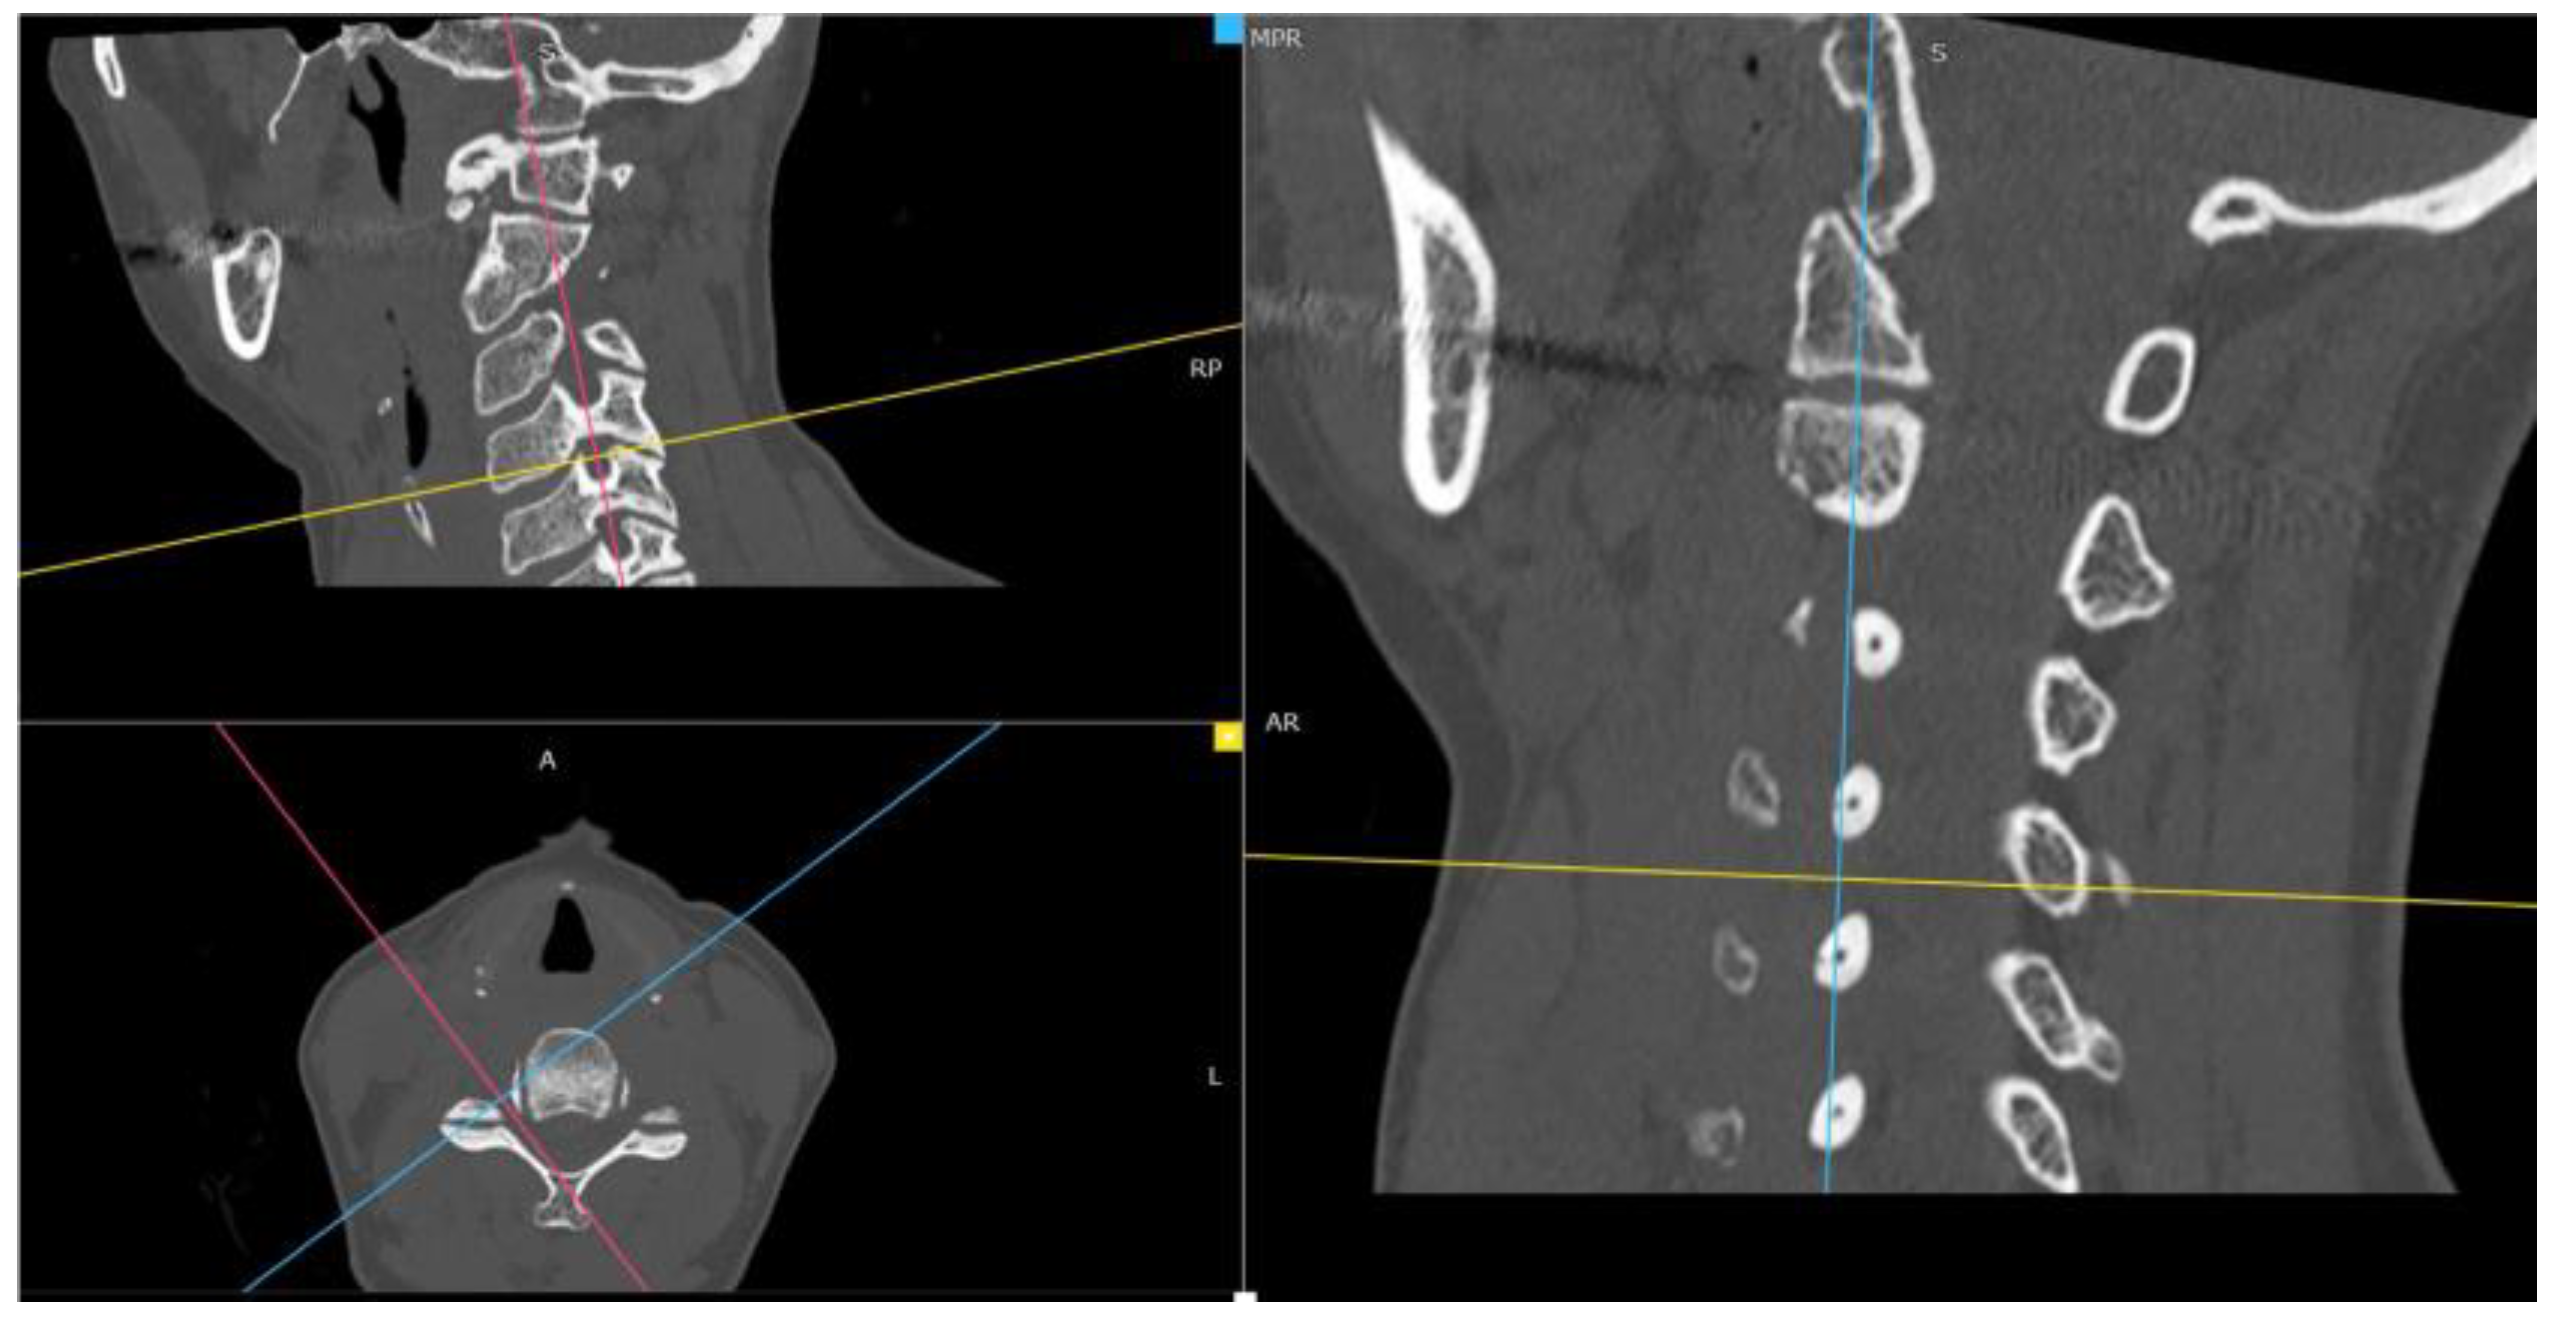

Through the use of MIP and MPR cervical bone-window CT scans, the correct site for measurements at each cervical segment (surgical or above or below) was selected matching the midline point on the anterior surface of the vertebral body on coronal view with the intervertebral foramen plane on axial view, and then adjusted with a plane parallel to the inferior endplate of the level above on the sagittal view. (Figure 1). The antero-posterior (A-P) and cranio-caudal (C-C) diameters of each foramen (surgical and adjacent levels, right and left) were manually measured (Figure 2a). The measurement of the C-C diameter was considered similar to the height of the foramen, and in sagittal reconstruction it was the distance between the midpoint of the upper and lower corresponding pedicles; the measurement of the A-P diameter was considered similar to the width of the foramen, and in sagittal reconstruction it was the distance between the anterior and the posterior border of the inferior intervertebral notch. For the intervertebral disc measurement, the disc height was measured in the anterior, middle, and posterior third on sagittal CT scans. The measure of the intervertebral disc space was considered from the corresponding point (anterior, middle, and posterior) of the inferior endplate of the upper vertebral body to the superior endplate of the lower vertebral body (Figure 2b). CT scans were performed before and within 72 h after surgery, usually the day after the procedure.

Figure 1. Neural cervical foramen was centered using MIP and MPR CT reconstructions.